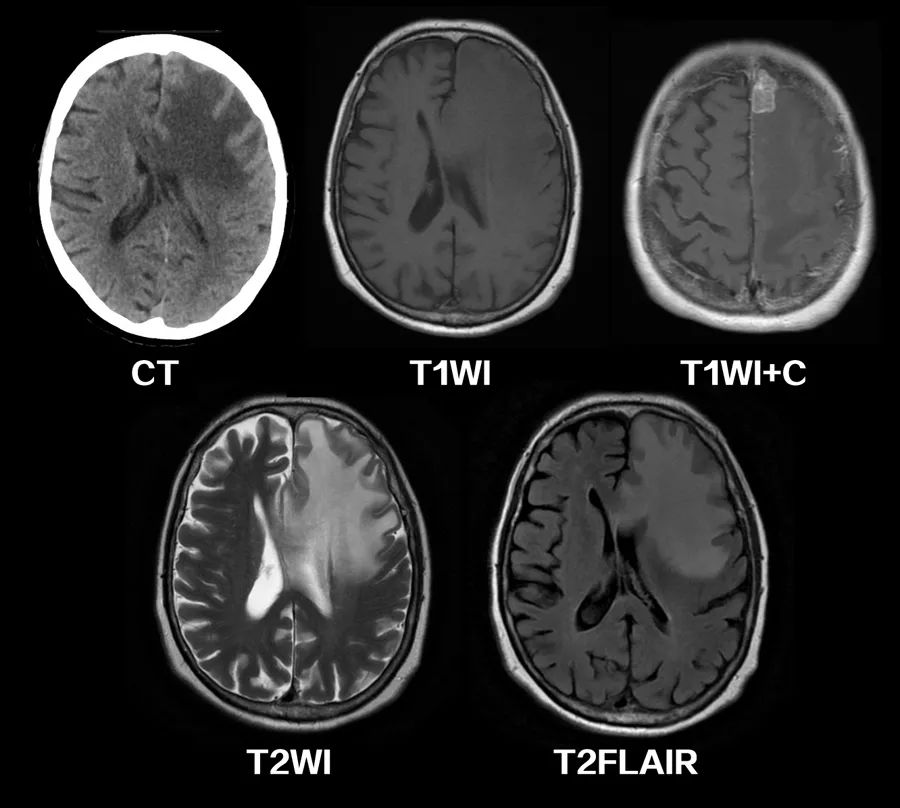

图4 乳腺癌脑转移,CT、MRI上可见广泛的血管源性脑水肿区域,侧脑室受压,中线移位。引起血管源性脑水肿的占位性病变位于左额上回。